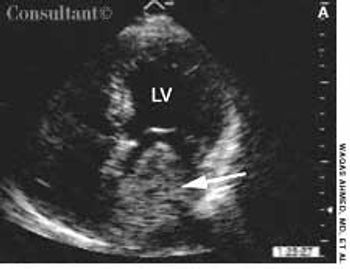

Police brought a delirious, combative 24-year-old man to the emergency department. The patient was unable to provide any history on arrival, but his scarred, blistering lips and his vital signs (blood pressure, 166/102 mm Hg; heart rate, 97 beats per minute; respiratory rate, 24 breaths per minute; and temperature, 38.2°C, or 100.9°F) led to a possible diagnosis of cocaine-induced delirium.